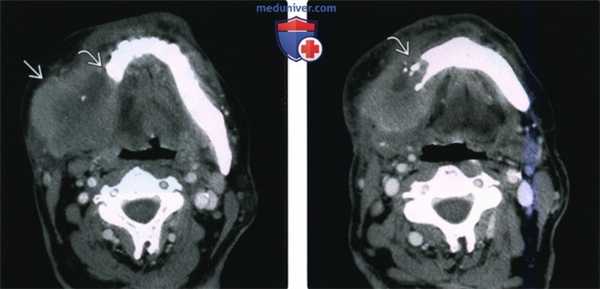

(Слева) КТ с КУ, аксиальная проекция. Злокачественная фиброзная гистиоцитома жевательного пространства и нижней челюсти. Солидная опухоль, которая умеренно накапливает контраст, располагается в правом жевательном пространстве и разрушает нижнюю челюсть, в том числе ее ветвь и тело. Жевательное пространство представляет собой глубокую область лица, в которой может возникать саркома.

(Справа) КТ с КУ, аксиальная проекция, тот же пациент. Солидная опухоль, умеренно накапливающая контраст, разрушает значительную часть нижней челюсти.

(Слева) На аксиальной КТ с КУ в жевательном пространстве справа визуализируется злокачественная фиброзная гистиоцитома нижней челюсти в виде минимально контрастирующегося солидного объемного образования, разрушающего ветвь и тело нижней челюсти. Жевательное пространство является известным местом возникновения сарком глубоких областей ли ца.

(Справа) На аксиальной КТ с КУ у этого же пациента визуализируется опухоль в жевательном пространстве справа, приводящая к обширной деструкции нижней челюсти. Обратите внимание на асимметрию лица на стороне поражения.